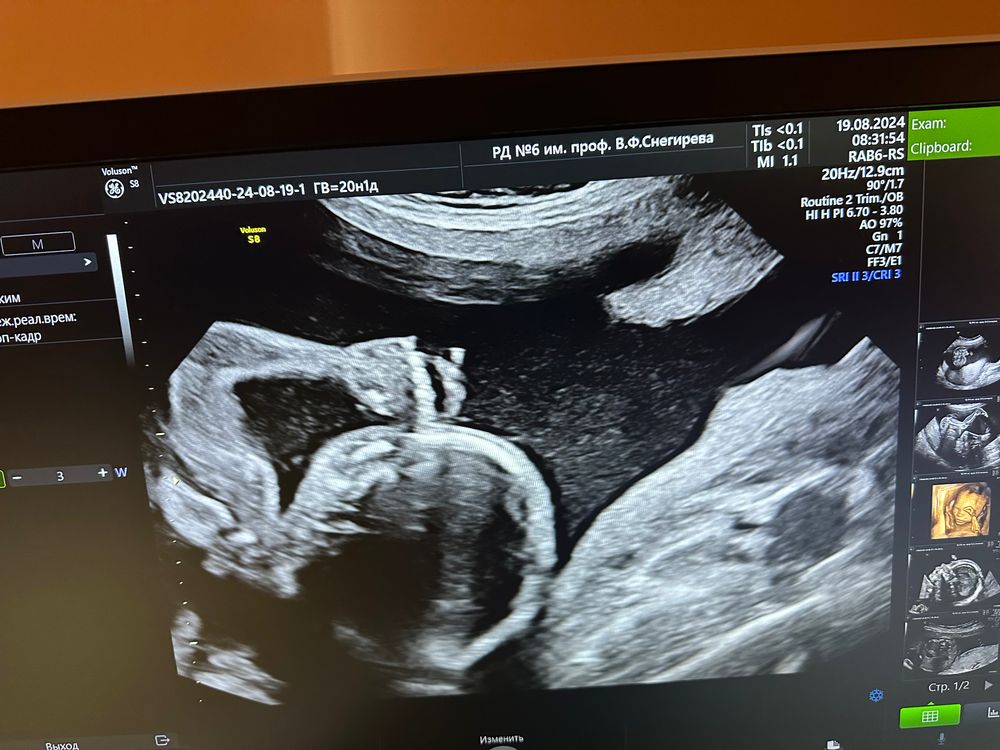

2 скрининг пройден

Такое фото потрясающее. Твк смотришь и не скажешь, что там всего 330 гр. Прям человечек)

Ну какой же симпатичный парень😊🤗